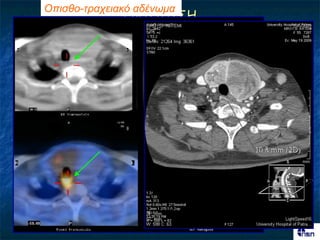

Οπηζζο-ηρατεηαθό αδέλφκα

Οπηζζο-οηζοθαγηθό αδέλφκα

Οπηζζο-ηρατεηαθό αδέλφκα ΓΝΣΟΠΙ΢Η Ονζόημπμ Mibi early Mibi late αδέκςμα; Pertechnetate Αθαίνεζε

Οπηζζο-οηζοθαγηθό αδέλφκα Πνώσμε 2 ώνεξ Φοπνόξ ζονεμεηδηθόξ όδμξ Όδμξ Αδέκςμα Tc-99m Αθαίνεζε